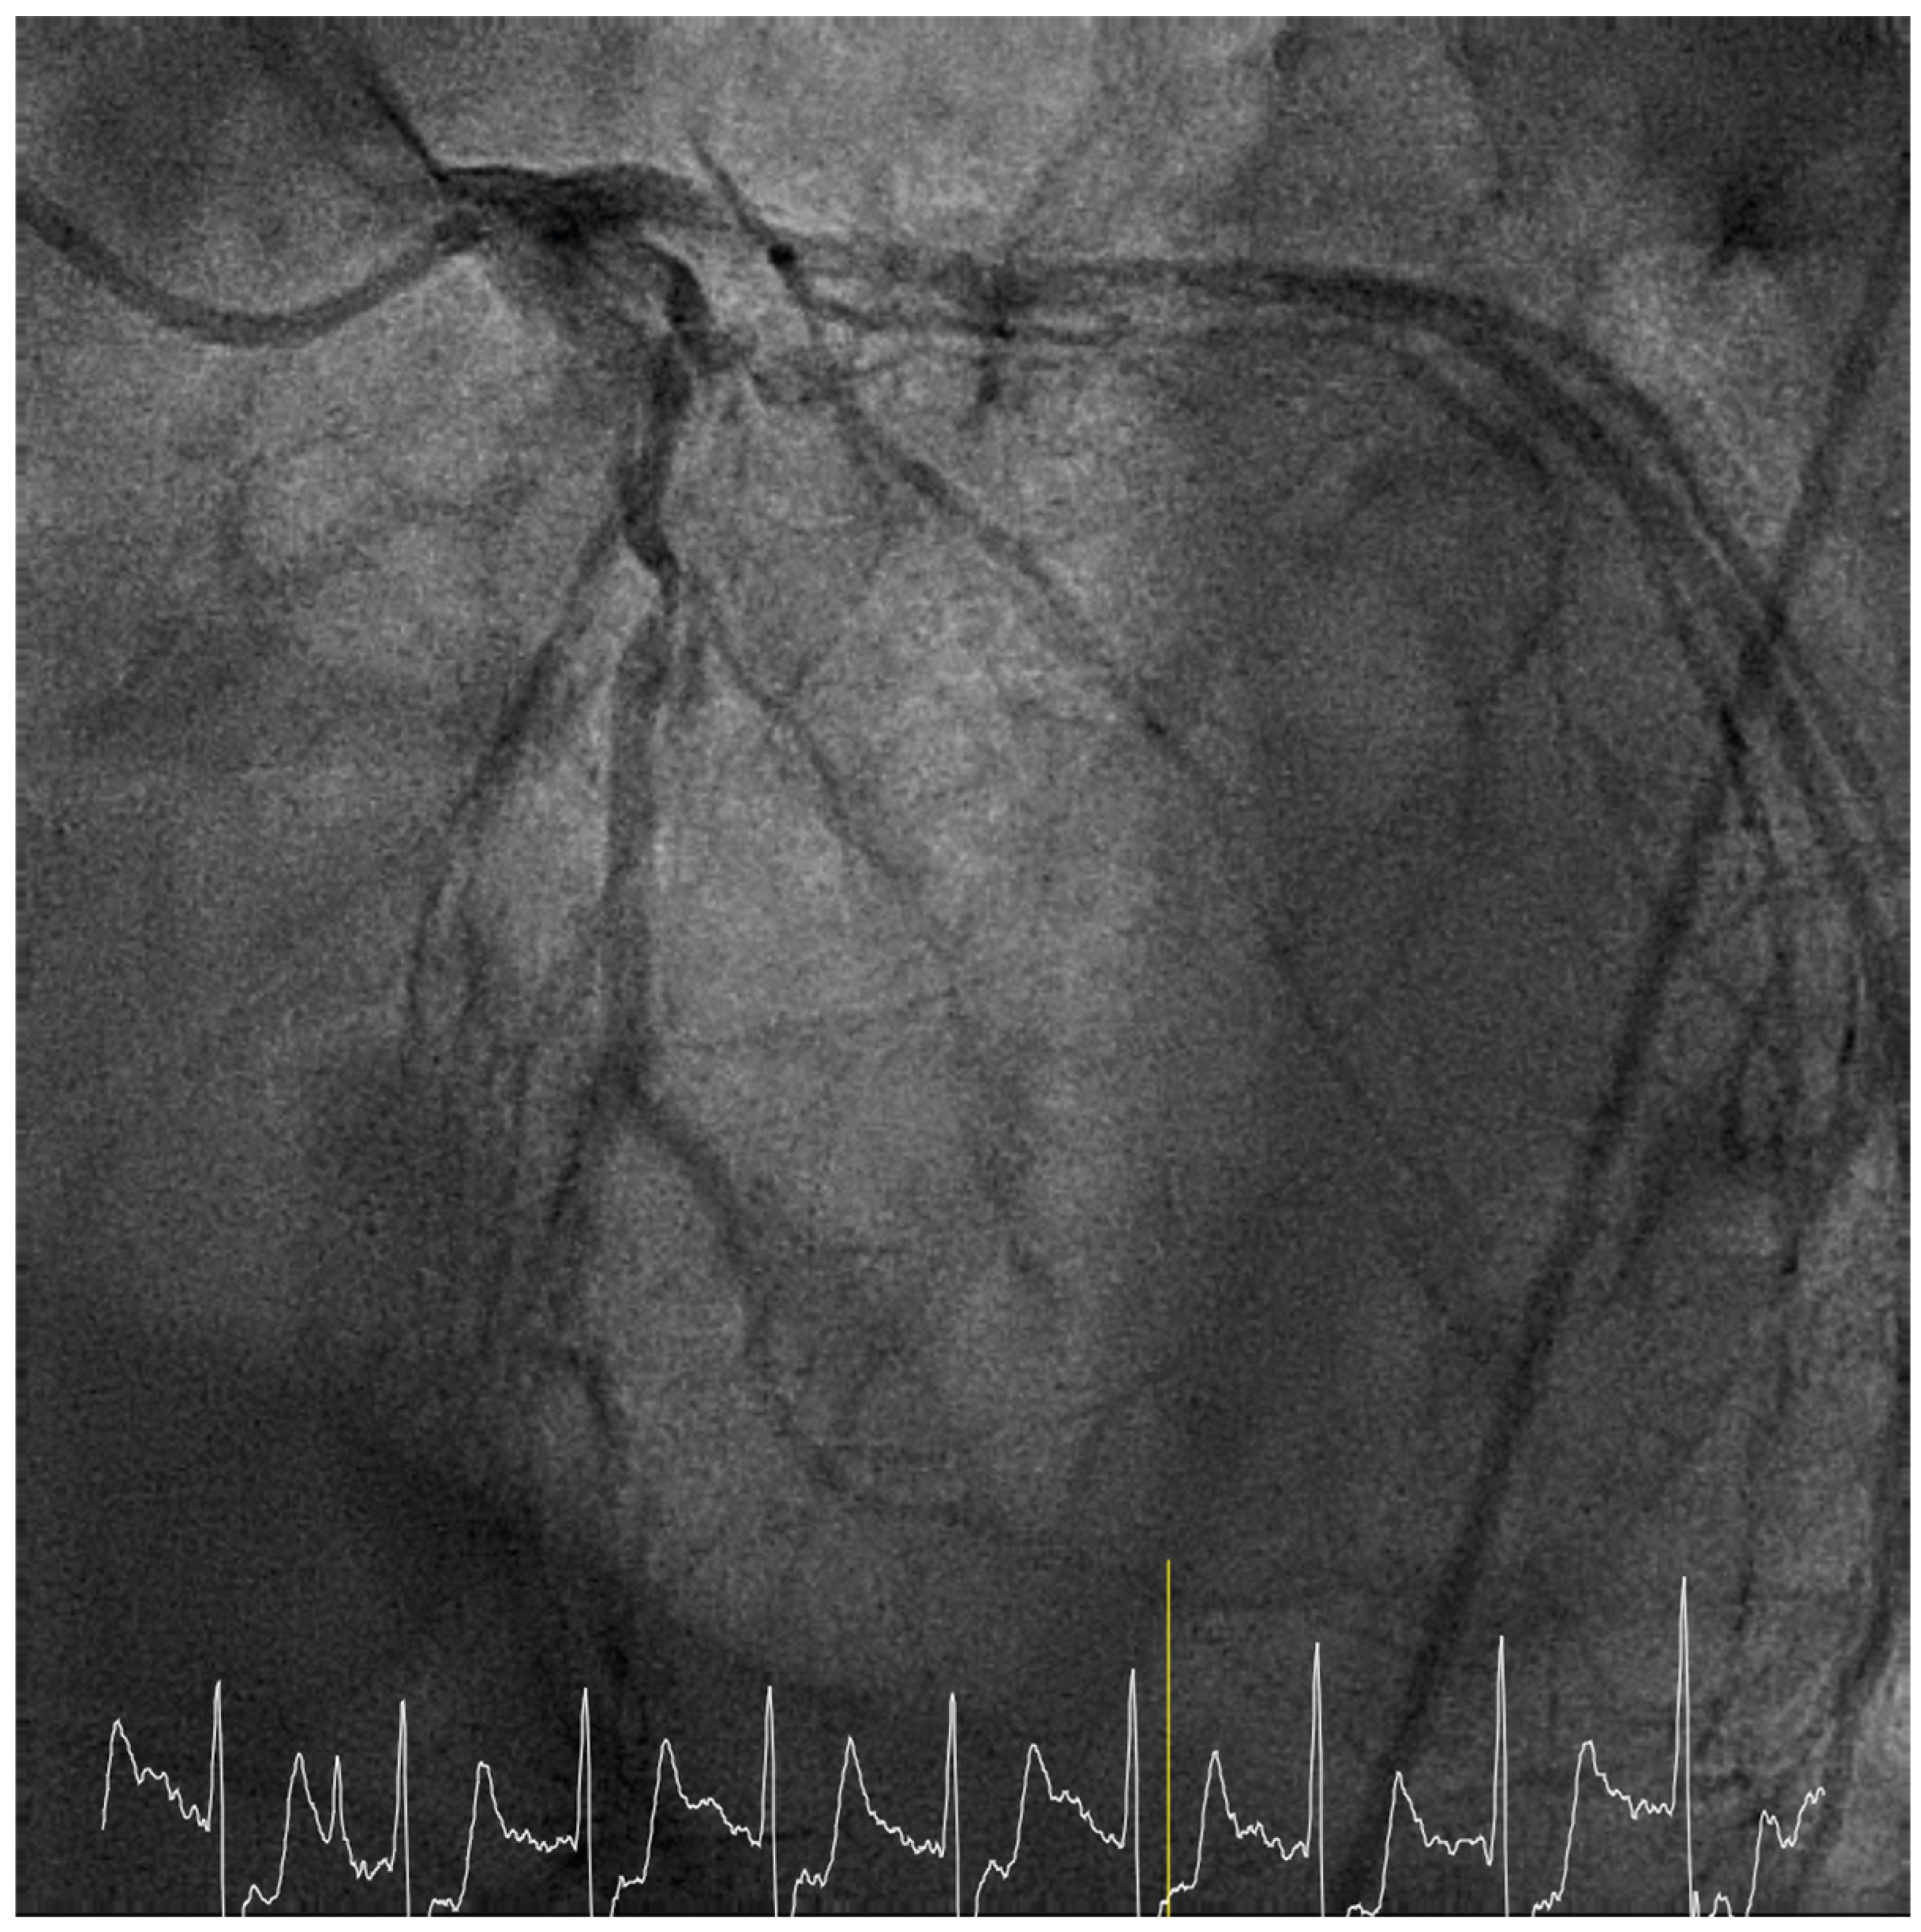

When the Chest Pain Suddenly Worsens

Case presentation

Solution